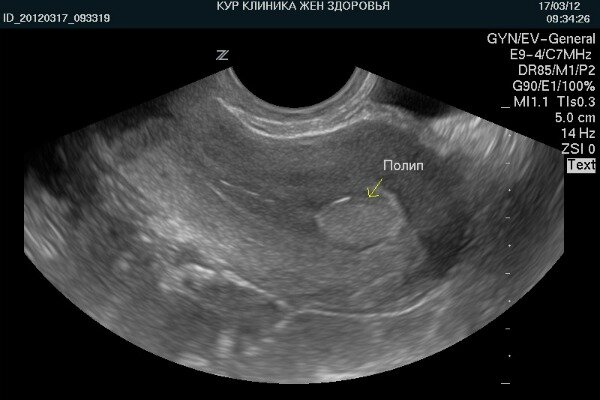

УЗИ — метод диагностики болезней шейки матки, который рекомендован всем женщинам старше 40 лет. Процедура способна выявить на ранних стадиях самое опасное и трудноизлечимое заболевание — рак. Она входит в стандарт обязательного обследования наряду с маммографией и ЭКГ. Также на УЗИ видны полипы и эрозии, которые являются фоновыми состояниями для развития злокачественных опухолей. Читайте на сайте...